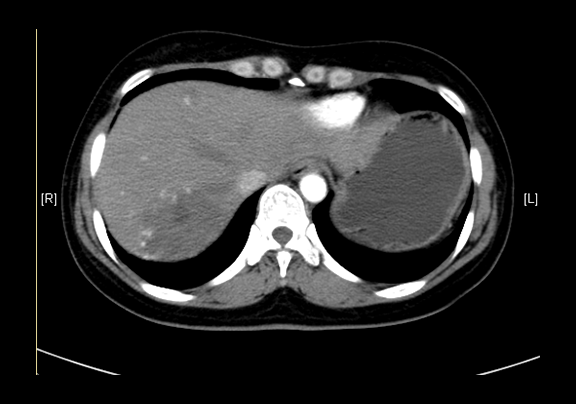

现病史:患者查体发现肝血管瘤半年,无腰背部放射痛、皮肤巩膜黄染、恶心、呕吐、寒战、高热、腹泻、血便、咳嗽、咳痰、胸闷、气短、尿频、尿急、尿痛、血尿,未予治疗。行上腹部增强CT示:肝血管瘤。

辅助检查: 下腹部增强CT示:肝内多发血管瘤可能性大,肝囊肿

术前CT检查:动脉期

静脉期

平衡期